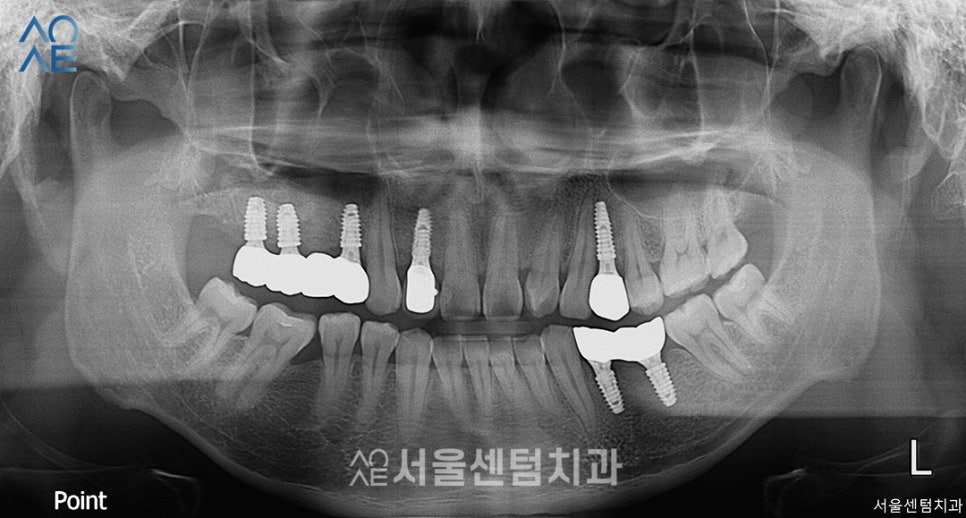

약 한달 뒤 촬영한 모습입니다.

다행히 잇몸뼈가 잘 형성되고 있는 모습입니다.

지난번 식립한 부분을 확인하면서

위-오른쪽 어금니에도 3개 추가 식립하였습니다.

역시나 뼈이식도 함께 진행하였습니다.

또 2주 뒤 세번째 수술을 진행합니다.

이번엔 아래-오른쪽 어금니입니다.

앞니 2차 수술과 보철물까지 장착한 후 입니다.

이 환자분은 위에 치아가 없다보니

아랫니가 올라온 상태여서

보철물을 수복할 공간이 부족한 편이었습니다.

따라서 공간을 만들어주는 교합조정술도 진행하고

보철물을 장착했습니다.